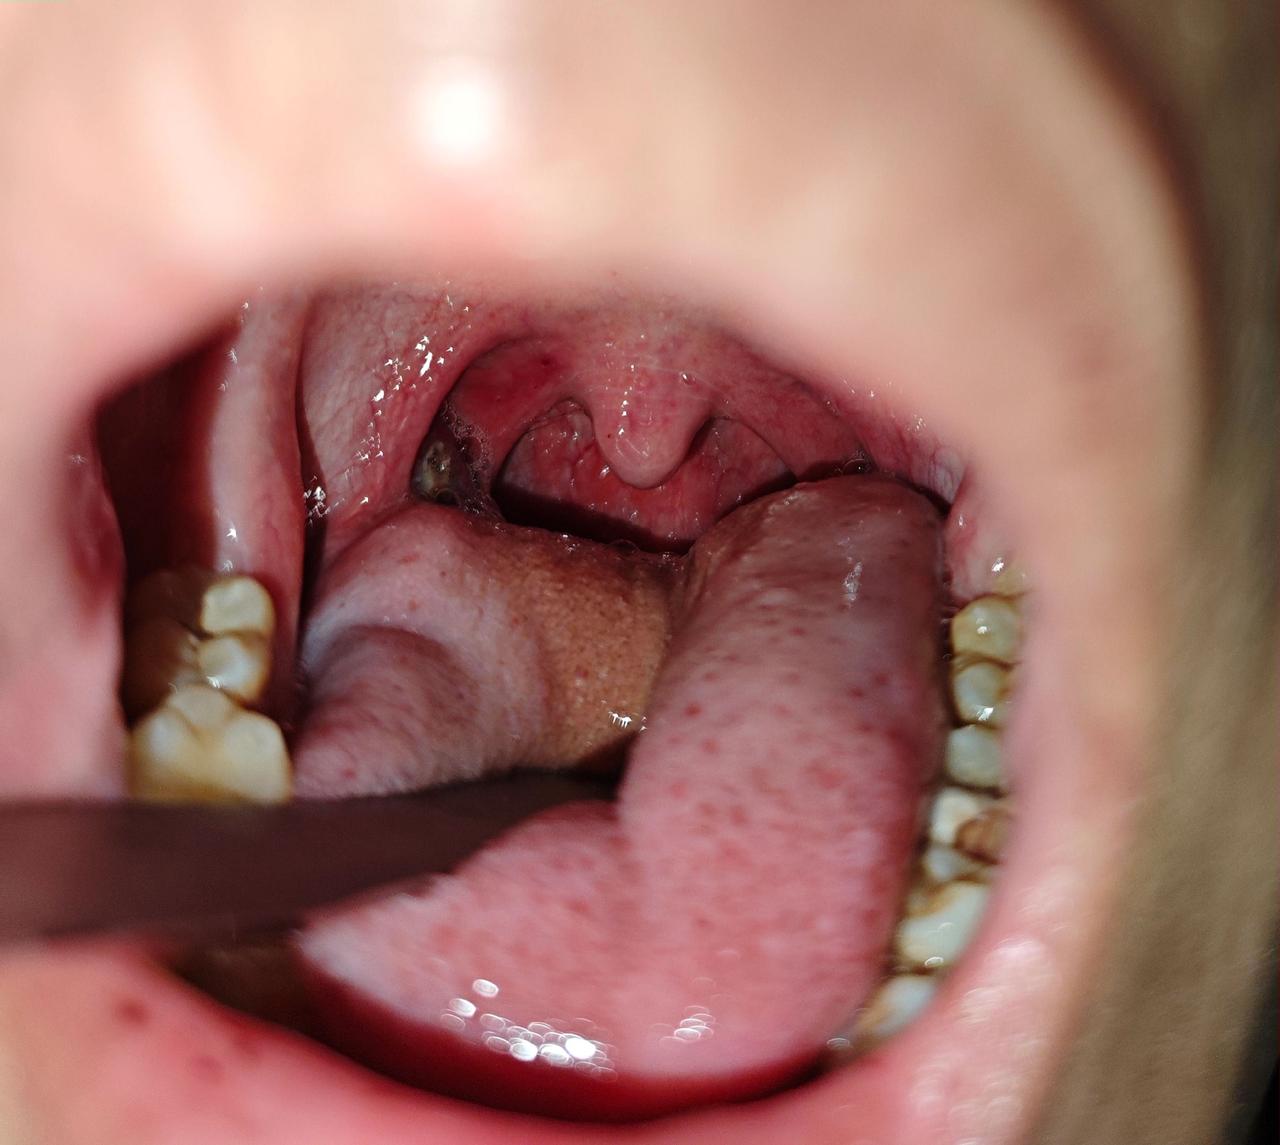

咽痛痰中带血丝今天门诊遇到一个18岁大一的男生,长得高高帅帅,患者的主诉就是右侧